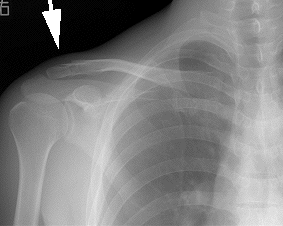

9月27日、丁度事故から3週間久々に病院に行った。レントゲンを見て、ペコちゃんに似た若

い女医は「幸運なことに真っ直ぐ付き始めています。普通だったら上にずれるので手術するんです

けど。」と意外そうに言う。これで一安心。接骨飯塚君の指導のもとテーピングで固めていたこと

はヒミツである。勿論診察には剥がしてテープの跡もアルコールで拭いていったがレントゲンしか

矢印が骨折箇所

テーピングでズレを押さえた状態